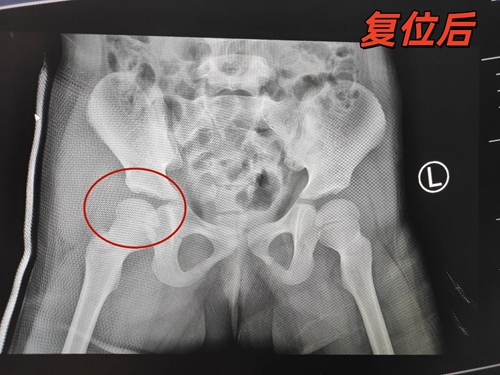

情急之下,家長(zhǎng)帶孩子火速趕往青島婦兒醫(yī)院。接診醫(yī)生仔細(xì)查看后緊急聯(lián)系了創(chuàng)傷中心醫(yī)生,醫(yī)生在綜合評(píng)估后做了一個(gè)大膽的決定:不用麻醉手術(shù),可以在創(chuàng)傷復(fù)蘇單元進(jìn)行手法復(fù)位!兩位醫(yī)生密切協(xié)作,憑借精準(zhǔn)的手法,僅用幾分鐘時(shí)間便復(fù)位成功,效果立竿見影,孩子的腿立馬不疼了,也敢活動(dòng)了。孩子?jì)寢寫抑男慕K于放下了。

所幸及時(shí)送醫(yī)進(jìn)行閉合復(fù)位,上述患兒免遭切開復(fù)位之苦。